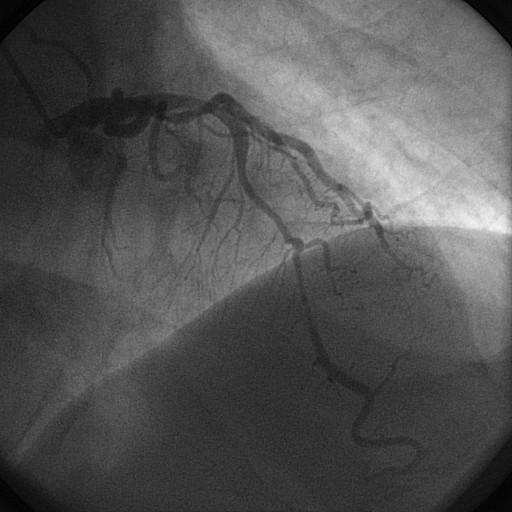

O músculo cardíaco é irrigado pelas artérias coronárias, que são vasos epicárdicos. Ponte miocárdica é uma anomalia congênita na qual um segmento da artéria coronária percorre um trajeto intramiocárdico com extensão e profundidade variáveis, ao invés de percorrer o seu trajeto epicárdico normal.

No post anterior discutimos a definição, prevalência, quadro clínico e diagnóstico / investigação de ponte miocárdica. Para discutirmos o tratamento, precisamos entender alguns fatores que podem estar associados ou que possam contribuir para o desenvolvimento dos sintomas ou isquemia em pacientes com ponte miocárdica.